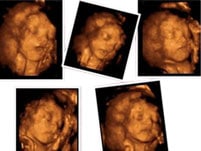

提前看到宝宝的模样 |

合肥中山医院斥资引进的GE-E8四维彩超,被誉为“神奇彩超”,能清晰观察胎儿各个部位发育情形,是筛查胎儿是否存在先天性畸形的专业设备。

★ 高清画质动态呈现

画质更清晰:中山医院引进的GE-E8四维彩超不仅画面清晰度高,画面的流畅细腻度,也是其他普通四维彩超不可比的。 |

角度更丰富:GE-E8四维彩超能够360度全方面观察宝宝动态,弥补了普通四维彩超动态显示角度不足的问题。 |